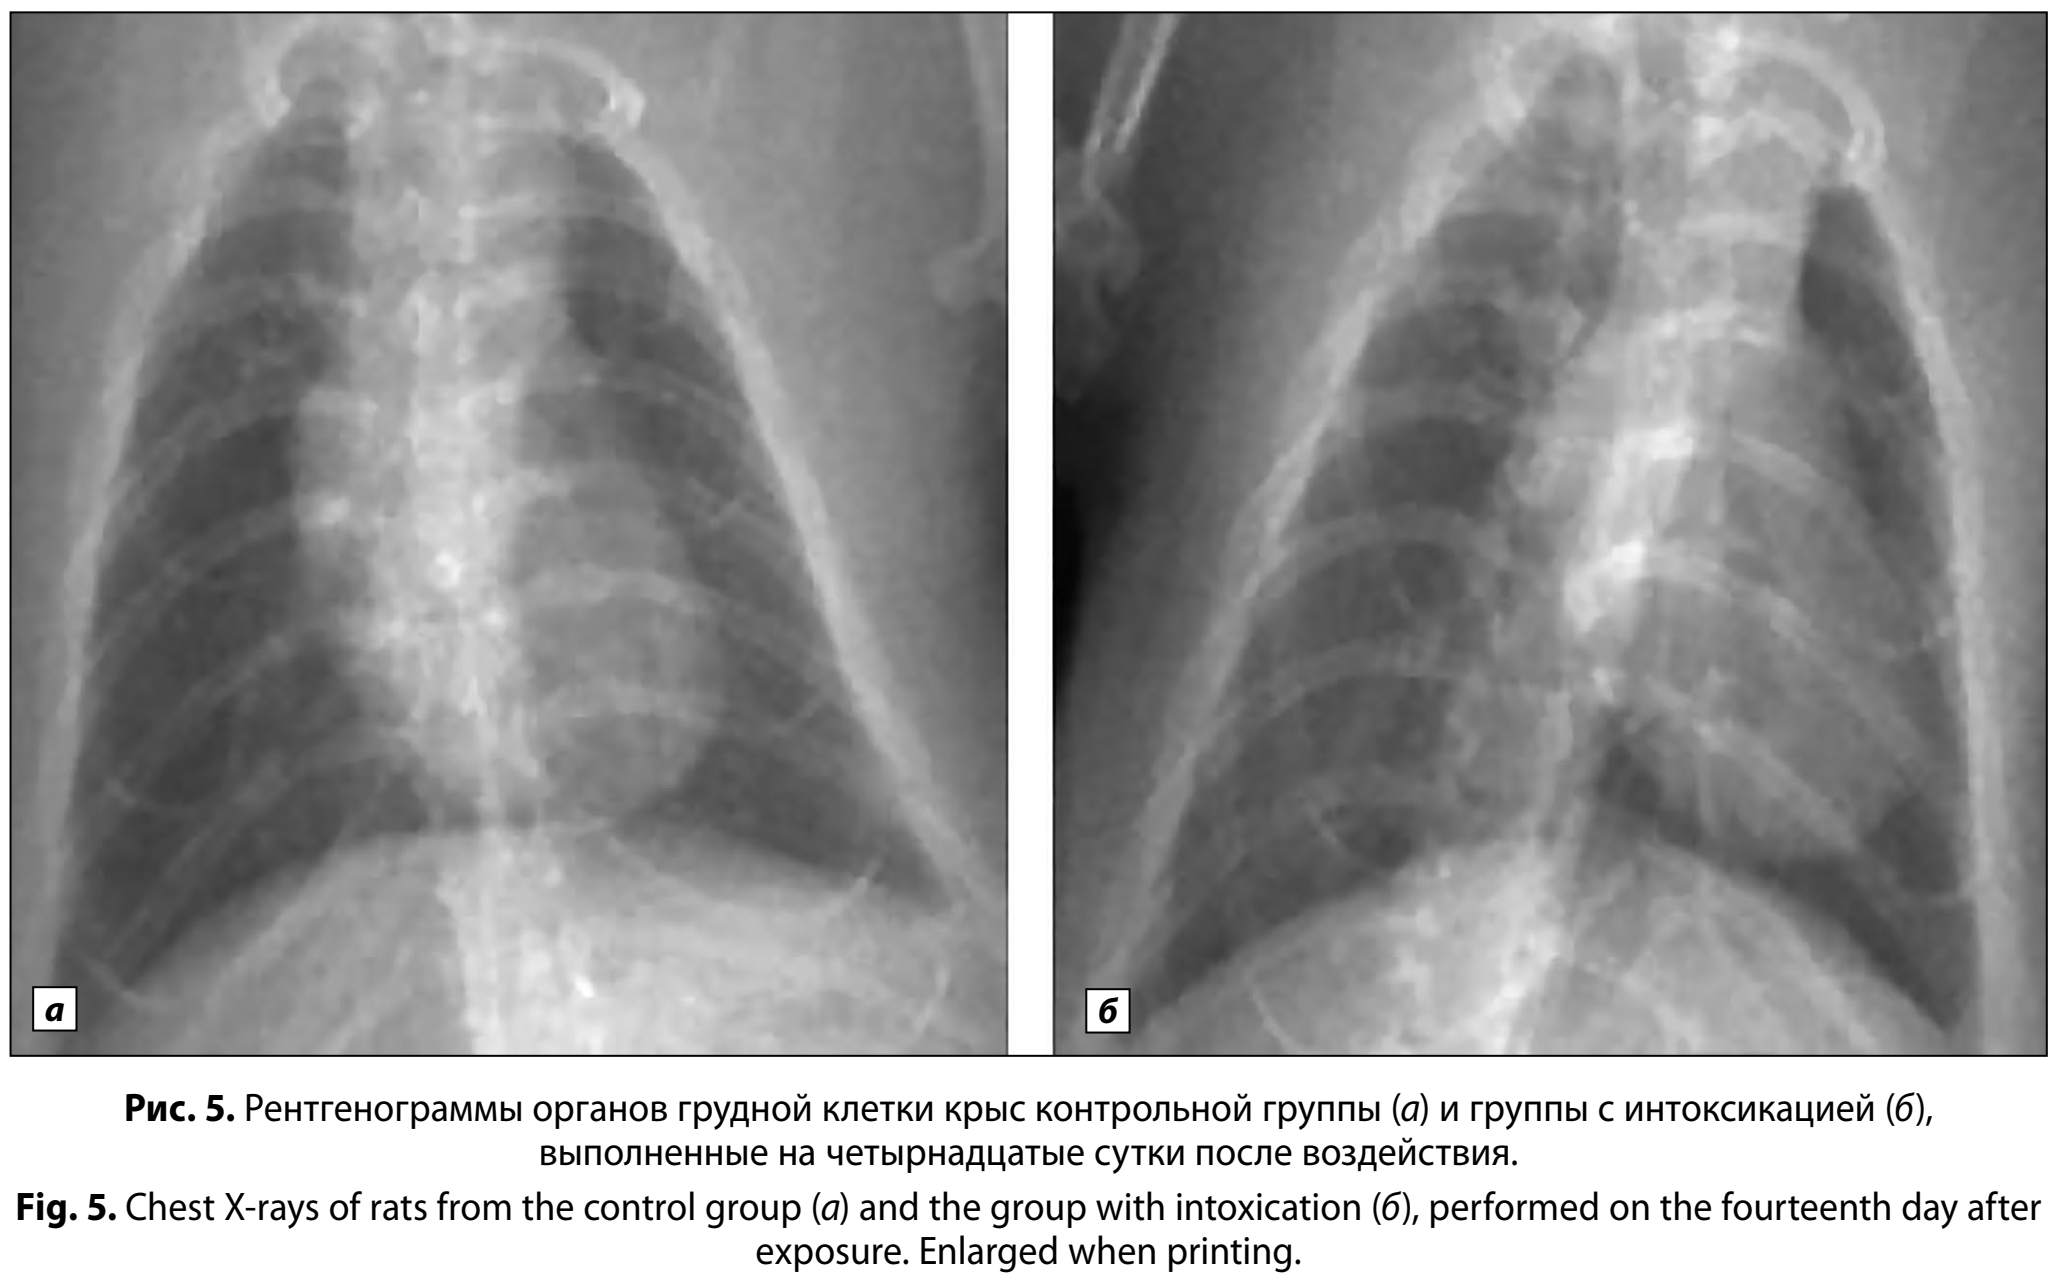

На 14-е сутки у выживших животных рентгенологически фиксировали полное разрешение ранее выявленных изменений (рис. 5, а, б). Лёгочные поля сохраняли равномерную прозрачность, патологические затемнения и признаки перибронхиальной инфильтрации отсутствовали. В контрольной группе на всех этапах исследования (1-е, 5-е и 14-е сутки) при рентгенографии определили равномерно прозрачные лёгочные поля без инфильтративных изменений.

К 14-м суткам после воздействия рентгенологическая картина у выживших животных демонстрировала восстановление прозрачности лёгочных полей и отсутствие инфильтративных изменений, что соответствовало данным контрольной группы. Однако при проведении макроскопического исследования были выявлены плотные тёмно-коричневые сливные зоны в прикорневых отделах, окружённые участками ателектазов.

У выживших животных на 14-е сутки после воздействия лёгочный коэффициент оставался повышенным, определялись признаки повреждения при гистологическом исследовании. Тем не менее при проведении рентгенологического исследования никаких изменений не выявили. Таким образом, рентгенологическое исследование органов грудной клетки не в полной мере отражает состояние тканей лёгких в отсроченном постинтоксикационном периоде.